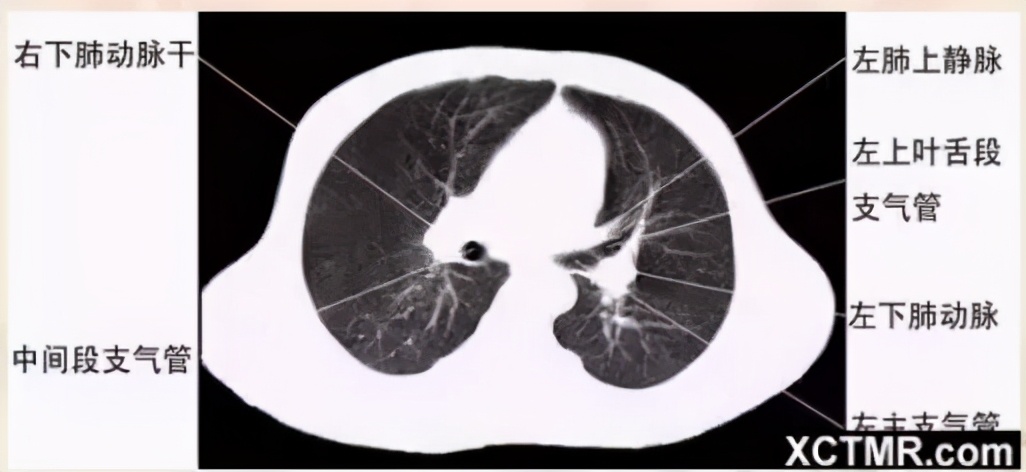

左主支气管层面